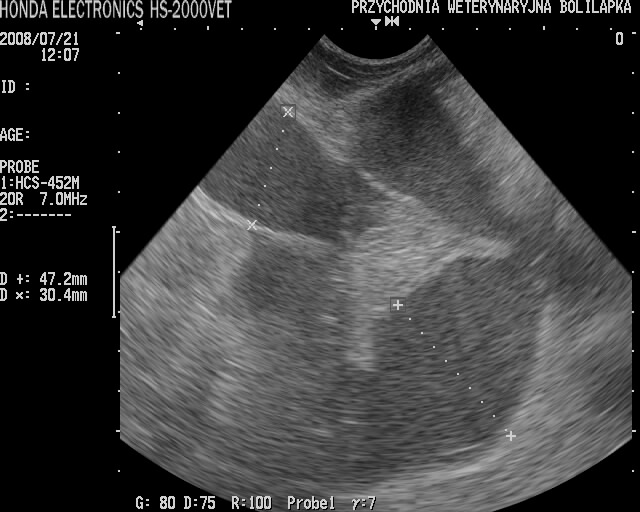

Oprócz badania klinicznego w celu rozpoznania stosuje się badania dodatkowe. Spośród badań obrazowych najbardziej przydatna jest ultrasonografia.

USG, poza potwierdzeniem choroby, pozwala również lekarzowi ocenić ścianę macicy oraz jej zawartość, co ma wpływ na wybór metody leczenia i rokowanie. Konieczne jest również badanie krwi (morfologia i biochemia), umożliwiające ocenę zaawansowania stanu zapalnego oraz stopień uszkodzenia innych narządów.